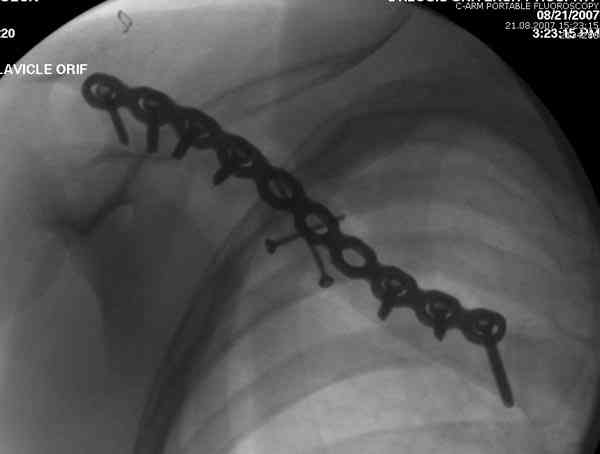

Второй случай тоже недавно оперирован по поводу

ложного сустава, в марте травма, через 4.5 половиной

операция..